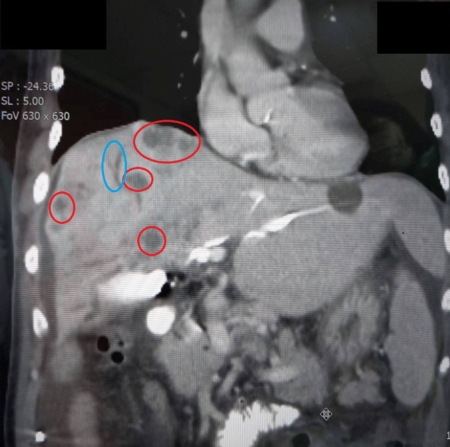

大千綜合醫院肝膽腸胃科醫師吳家慶表示,此次案例因抽血檢查呈現肝功能指數與膽紅素(黃疸指數)都非常高,進一步安排腹部超音波及電腦斷層檢查,赫然發現肝臟佈滿腫瘤、肝內膽管與總膽管異常擴張、肺部也疑似轉移腫瘤,因此高度懷疑是晚期肝癌或膽管癌,後經病理報告確認為膽管癌。由於病人的黃疸指數過高,膽汁無法排出,若不及時處理恐引發感染,所以先由放射科醫師進行「經皮穿肝膽道引流術」,從皮膚穿刺至肝臟膽管中,引流滯留的膽汁,來減輕黃疸症狀。後續考量引流管需要長期留置,為不影響病人的生活品質,故採用「內視鏡逆行性膽道引流術」,改以體內放置引流管,減少外部管路帶來的不便與感染風險。